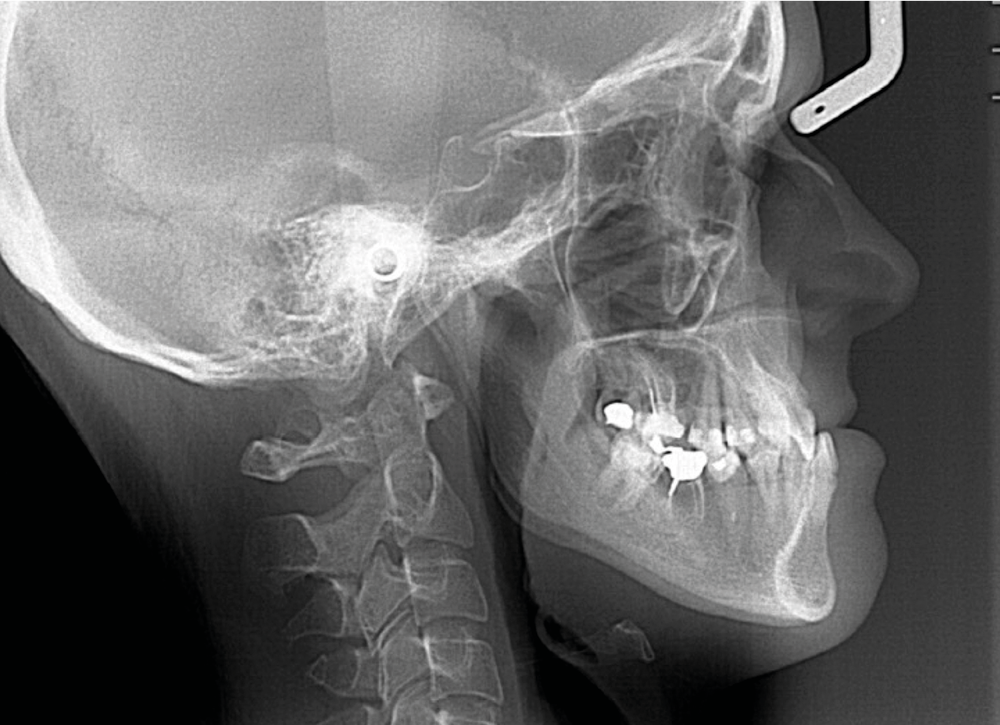

Diagnostic (fig. 1a-g)

La patiente présente une classe III squelettique dans un contexte hyperdivergent associée à une endoalvéolie maxillaire, un articulé inversé antérieur, une rétroversion incisive maxillaire, des rapports de classe I canine bilatérale, une absence de 16 et 36.

Au niveau esthétique, le profil est rectiligne. La lèvre supérieure est plus effacée, en retrait par rapport à la lèvre inférieure. De face et de profil, la mandibule paraît massive et le maxillaire effacé : le manque de soutien de la lèvre supérieure contribue à cette impression.

Au niveau fonctionnel, il existe un pro-glissement mandibulaire et un articulé inversé antérieur. Le profil téléradiographique montre en occlusion des rapports labiaux et un profil de classe III plus marqué que sur photographies.